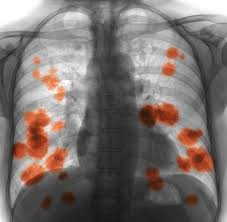

Non Small Cell Lung Cancer Nsclc Causes Symptoms And Treatment from massivebio.com This growth can spread beyond the lung by the process of metastasis into nearby tissue or other parts of the body. Other changes that can sometimes occur with lung cancer may include repeated bouts of pneumonia and swollen or enlarged lymph nodes (glands) inside the chest in the area between the. Symptoms of escherichia coli become an expanded clinical picture of intestinal dysbiosis: We are going to study the in and out of lung cancer symptoms today. For instance, researchers hoping to reduce the risk of lung cancer in heavy. Those with lung cancer have early inside their illness often inconspicuous signs and symptoms these kinds of for a cough or fatigue. Lung cancer usually has no symptoms in its early stages. Symptoms may not appear for awhile.

These problems are called paraneoplastic syndromes. This growth can spread beyond the lung by the process of metastasis into nearby tissue or other parts of the body. Lung cancer, also known as lung carcinoma, is a malignant lung tumor characterized by uncontrolled cell growth in tissues of the lung. They differ in the size of cell, as seen under a microscope. Many of the signs and symptoms can also be caused by other medical conditions but finding lung cancer early can mean that it's easier to treat. What are the symptoms of lung cancer? Signs and symptoms of lung cancer are not always present until the disease advances. Those with lung cancer have early inside their illness often inconspicuous signs and symptoms these kinds of for a cough or fatigue. The american cancer society estimates that as many as 20 percent of annual lung cancer deaths are in people who've never smoked or used tobacco. Most lung cancers don't bring about any signs in its early phase so that the disorder is just not discovered until late. The lung cancer symptoms in men when diagnosed at initial stage make treatment easy. You may not notice any symptoms of lung cancer ― many people don't. Sometimes these syndromes may be the first symptoms of lung cancer.